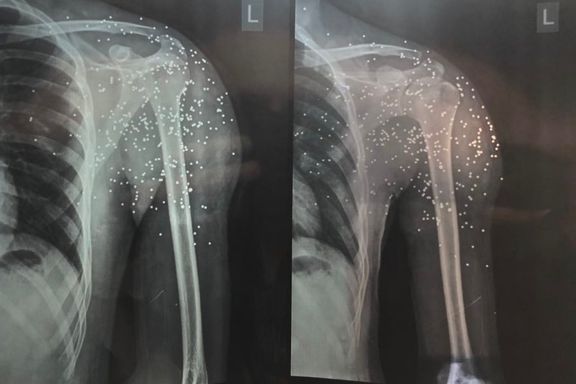

He said if he fails to refer them to his trusted doctors in Iran, he tries to walk them through the best home remedies possible. According to him, their injuries range from fractures and significant head injuries, to second- and third-degree burns from electric batons, as well as bullet and pellet wounds.